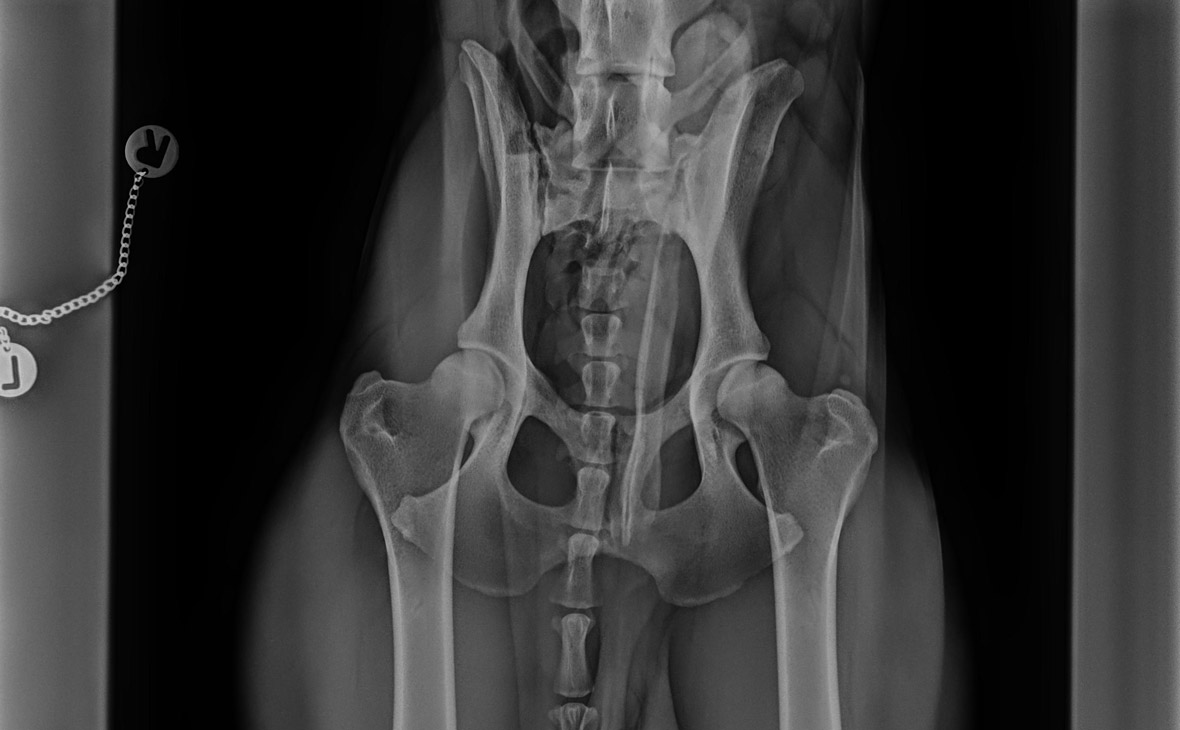

Lass uns mal bei Klausi anfangen. Wir haben den Kerl übernommen, als er anderthalb Jahre alt war. Damals hieß es: „HD und ED? Alles top, wurde untersucht!“ Aber – und hier ist der erste wichtige Punkt für dich – wir haben nie ein Röntgenbild gesehen. Wir haben nachgefragt, wieder und wieder, aber da kam nichts.

Ich wollte aber wissen, woran wir sind. Also ab zum Tierarzt, Röntgenbilder machen lassen (Zahnreinigung gab es direkt im Abwasch dazu, wenn er schon mal in Narkose lag). Und siehe da: Die Tierärztin sah erste Anzeichen für eine Hüftdysplasie Hund. Auch beim Ellbogen gab es Hinweise, dass das Gelenk in Zukunft Probleme machen könnte.

Das war ein Schlag in die Magengrube, weil Klausi im Alltag absolut nichts gezeigt hat. Er ist gesprungen, ist gerannt, war topfit. Aber genau das ist die Falle! Man lässt sich so schnell beruhigen, wenn man das Tier sieht. Heute, mit fast fünf Jahren, merke ich, dass dieses frühe Röntgen extrem wichtig war. Ich sehe heute die Kleinigkeiten: Er braucht nach dem Schlafen länger, um „rund“ zu laufen. Er überlegt zweimal, ob er springt. Hätten wir damals nicht hingeschaut, hätten wir seinen Körper vielleicht schon längst über die Kante getrieben.

Hüftdysplasie Hund: Das mechanische Problem

Stell dir das Hüftgelenk wie ein Kugelgelenk vor. Da gibt es den Hüftkopf und die Hüftpfanne. Bei einem gesunden Hund sitzt dieser Kopf bombenfest und sauber in der Pfanne. Wenn wir aber über die Hüftdysplasie Hund reden, dann passt das Ganze einfach nicht optimal zusammen. Der Kopf wackelt, sitzt locker oder die Pfanne ist zu flach.

Durch diese Instabilität entsteht Reibung. Und Reibung im Gelenk ist der Feind. Sie führt zu Verschleiß, und Verschleiß führt am Ende fast immer zu Arthrose. Das Gelenk verändert sich, es bilden sich knöcherne Zubildungen, und irgendwann tut jeder Schritt weh.